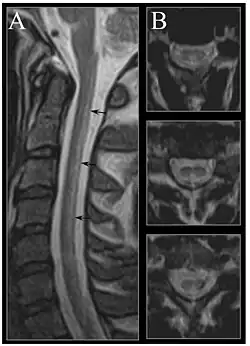

| Image of the cervical spinal cord in vitamin B12 deficiency showing subacute combined degeneration. (A) The midsagittal T2-weighted image shows linear hyperintensity in the posterior portion of the cervical tract of the spinal cord (black arrows). (B) Axial T2-weighted images reveal the selective involvement of the posterior columns. | |

Severe vitamin B12 deficiency is associated with subacute combined degeneration of the spinal cord, which involves demyelination of the posterior and lateral columns of the spinal cord.[101] Symptoms include memory and cognitive impairment, sensory loss, motor disturbances, personality changes, disorientation, irritability, dementia, loss of posterior column functions and disturbances in proprioception.[102][103][104] In advanced stages of vitamin B12 deficiency, cases of psychosis, paranoia and severe depression have been observed, which may lead to permanent disability if left untreated.[101][102][103] Studies have shown the rapid reversal of the neurological symptoms of vitamin B12 deficiency, after treatment with high-dose of vitamin B12 supplementation; suggesting the importance of prompt treatment in reversing neurological manifestations.[105]

MRI of the brain may show periventricular white matter abnormalities. MRI of the spinal cord may show linear hyperintensity in the posterior portion of the cervical tract of the spinal cord, with selective involvement of the posterior columns.